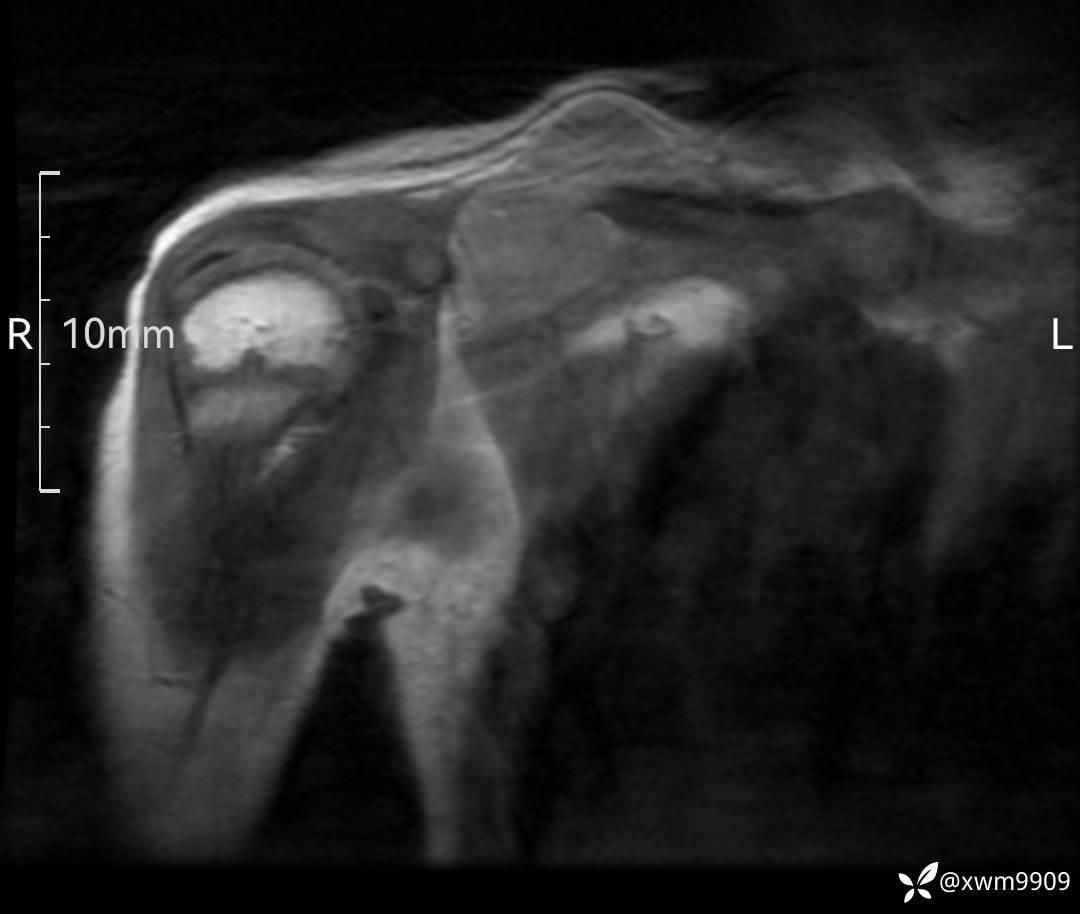

DR:

CT:

2、CT、MR肿块内可见液-液平面,常见有哪些疾病。